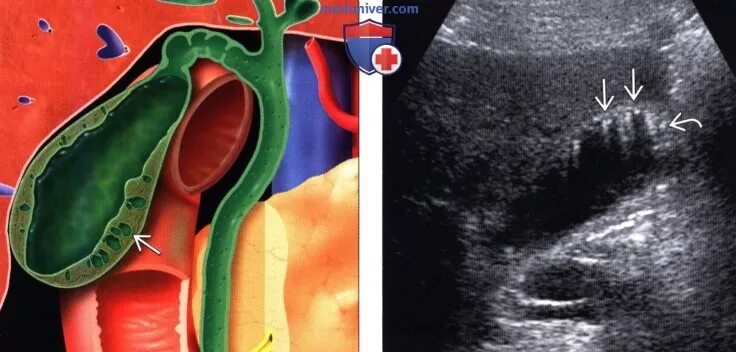

Стенка желчного уплотнена что это